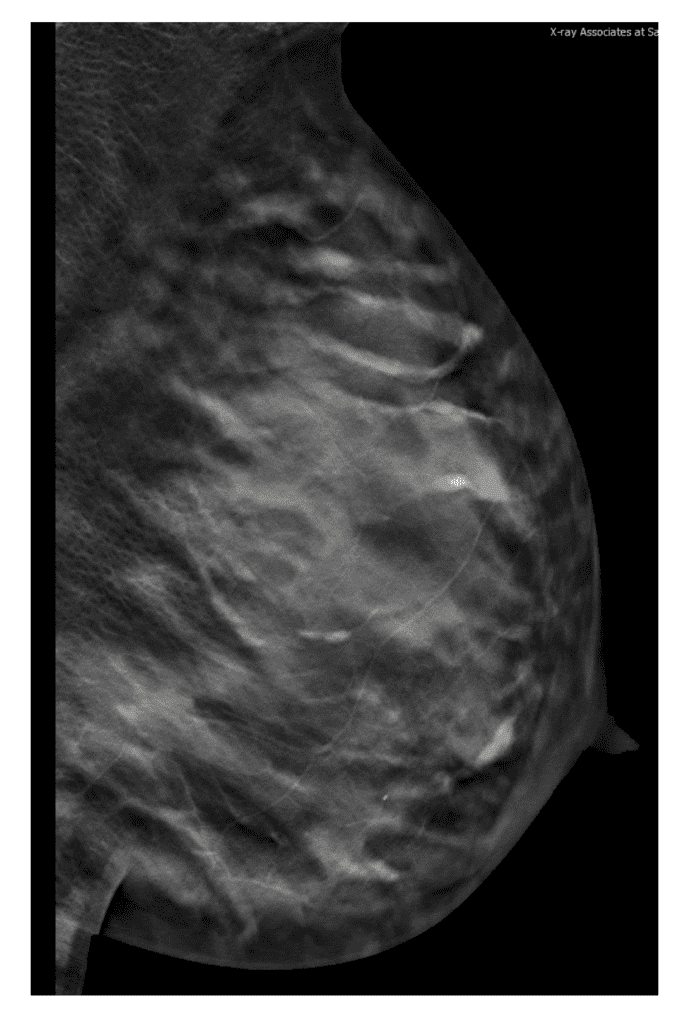

Tomosynthesis (3D) mammogram during lactation in BRCA I patient.